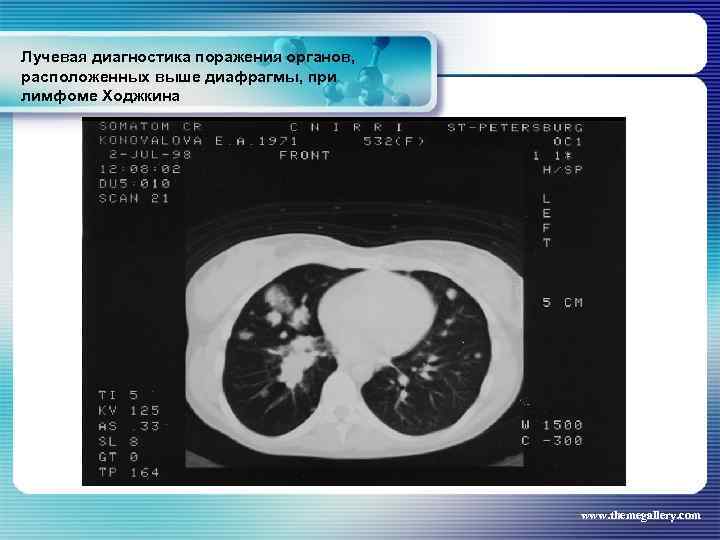

Лучевая диагностика поражения органов, расположенных выше диафрагмы, при лимфоме Ходжкина Частота поражения органов грудной полости при лимфоме Ходжкина: поражение средостения легких плевры грудной стенки - 66, 7 % 33, 75% 5, 3% 1, 8% www. themegallery. com

Лучевая диагностика поражения органов, расположенных выше диафрагмы, при лимфоме Ходжкина Частота поражения органов грудной полости при лимфоме Ходжкина: поражение средостения легких плевры грудной стенки - 66, 7 % 33, 75% 5, 3% 1, 8% www. themegallery. com

Лучевая диагностика поражения органов, расположенных выше диафрагмы, при лимфоме Ходжкина www. themegallery. com

Лучевая диагностика поражения органов, расположенных выше диафрагмы, при лимфоме Ходжкина www. themegallery. com

Лучевая диагностика поражения органов, расположенных выше диафрагмы, при лимфоме Ходжкина www. themegallery. com

Лучевая диагностика поражения органов, расположенных выше диафрагмы, при лимфоме Ходжкина www. themegallery. com

Лучевая диагностика поражения органов, расположенных выше диафрагмы, при лимфоме Ходжкина www. themegallery. com

Лучевая диагностика поражения органов, расположенных выше диафрагмы, при лимфоме Ходжкина www. themegallery. com

Лучевая диагностика поражения органов, расположенных выше диафрагмы, при лимфоме Ходжкина www. themegallery. com

Лучевая диагностика поражения органов, расположенных выше диафрагмы, при лимфоме Ходжкина www. themegallery. com

Лучевая диагностика поражения органов, расположенных выше диафрагмы, при лимфоме Ходжкина www. themegallery. com

Лучевая диагностика поражения органов, расположенных выше диафрагмы, при лимфоме Ходжкина www. themegallery. com

Лучевая диагностика поражения органов, расположенных выше диафрагмы, при лимфоме Ходжкина www. themegallery. com

Лучевая диагностика поражения органов, расположенных выше диафрагмы, при лимфоме Ходжкина www. themegallery. com

Лучевая диагностика поражения органов, расположенных выше диафрагмы, при лимфоме Ходжкина www. themegallery. com

Лучевая диагностика поражения органов, расположенных выше диафрагмы, при лимфоме Ходжкина www. themegallery. com

Лучевая диагностика поражения органов, расположенных выше диафрагмы, при лимфоме Ходжкина www. themegallery. com

Лучевая диагностика поражения органов, расположенных выше диафрагмы, при лимфоме Ходжкина www. themegallery. com

Лучевая диагностика поражения органов, расположенных выше диафрагмы, при лимфоме Ходжкина www. themegallery. com

Лучевая диагностика поражения органов, расположенных выше диафрагмы, при лимфоме Ходжкина www. themegallery. com

Лучевая диагностика поражения органов, расположенных выше диафрагмы, при лимфоме Ходжкина www. themegallery. com

Лучевая диагностика поражения органов, расположенных выше диафрагмы, при лимфоме Ходжкина www. themegallery. com

Лучевая диагностика поражения органов, расположенных выше диафрагмы, при лимфоме Ходжкина www. themegallery. com

Лучевая диагностика поражения органов, расположенных выше диафрагмы, при лимфоме Ходжкина www. themegallery. com

Лучевая диагностика поражения органов, расположенных выше диафрагмы, при лимфоме Ходжкина www. themegallery. com

Лучевая диагностика поражения органов, расположенных выше диафрагмы, при лимфоме Ходжкина www. themegallery. com